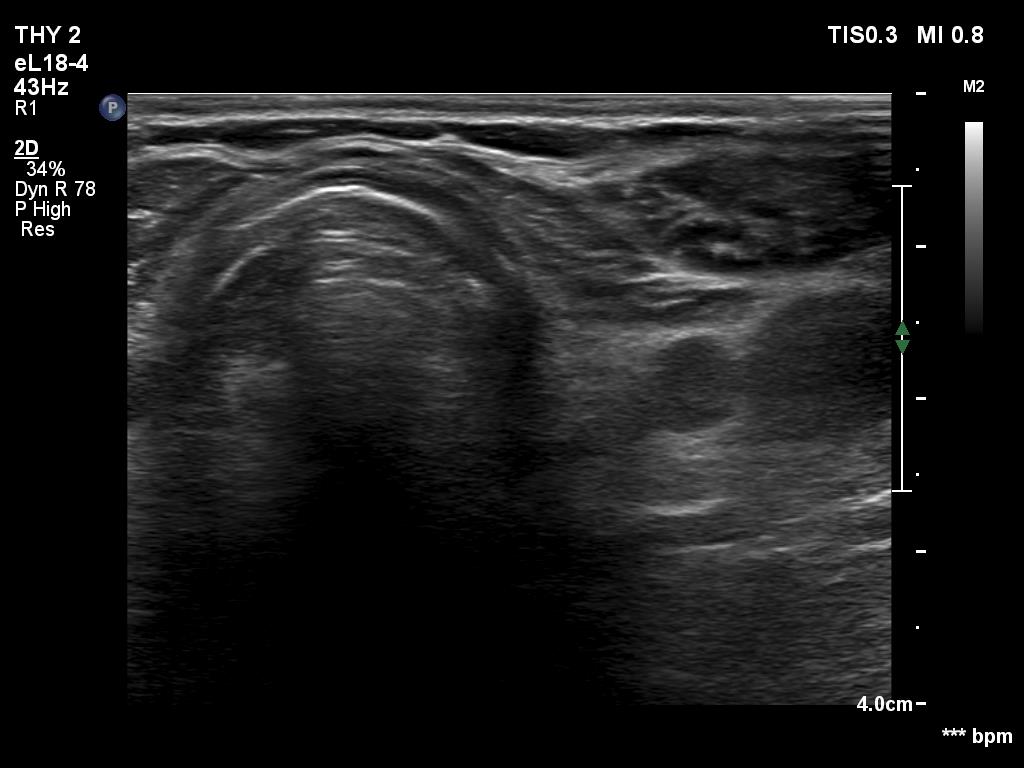

One month after surgery (second row of images):

Clinical data: The patient had no complaints.

Palpation: There was a relatively large, painless mass in the left thyroid bed.

Result of blood test: euthyroidism on daily 125 microgram levothyroxine (TSH 0.87 mIU/L).

Ultrasonography. The thyroid parenchyma was replaced by regenerative tissue. There was a cystic lesion in the left thyroid bed with a maximal diameter of 23 mm.